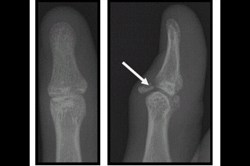

Mallet Finger